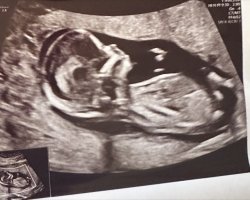

det burde være veldig tydelig så langt på vei, men bilde er ikke det beste. har du flere bilder?

Oul i dag viste jente! So vi hadde rett!hvis man skal gjette ut i fra disse bildene ville jeg ha tippet litt mer sannsynlighet for jente.

Gratulerer med guttBekreftet gutt på OUL Så dere som gjetta hadde rett![]()